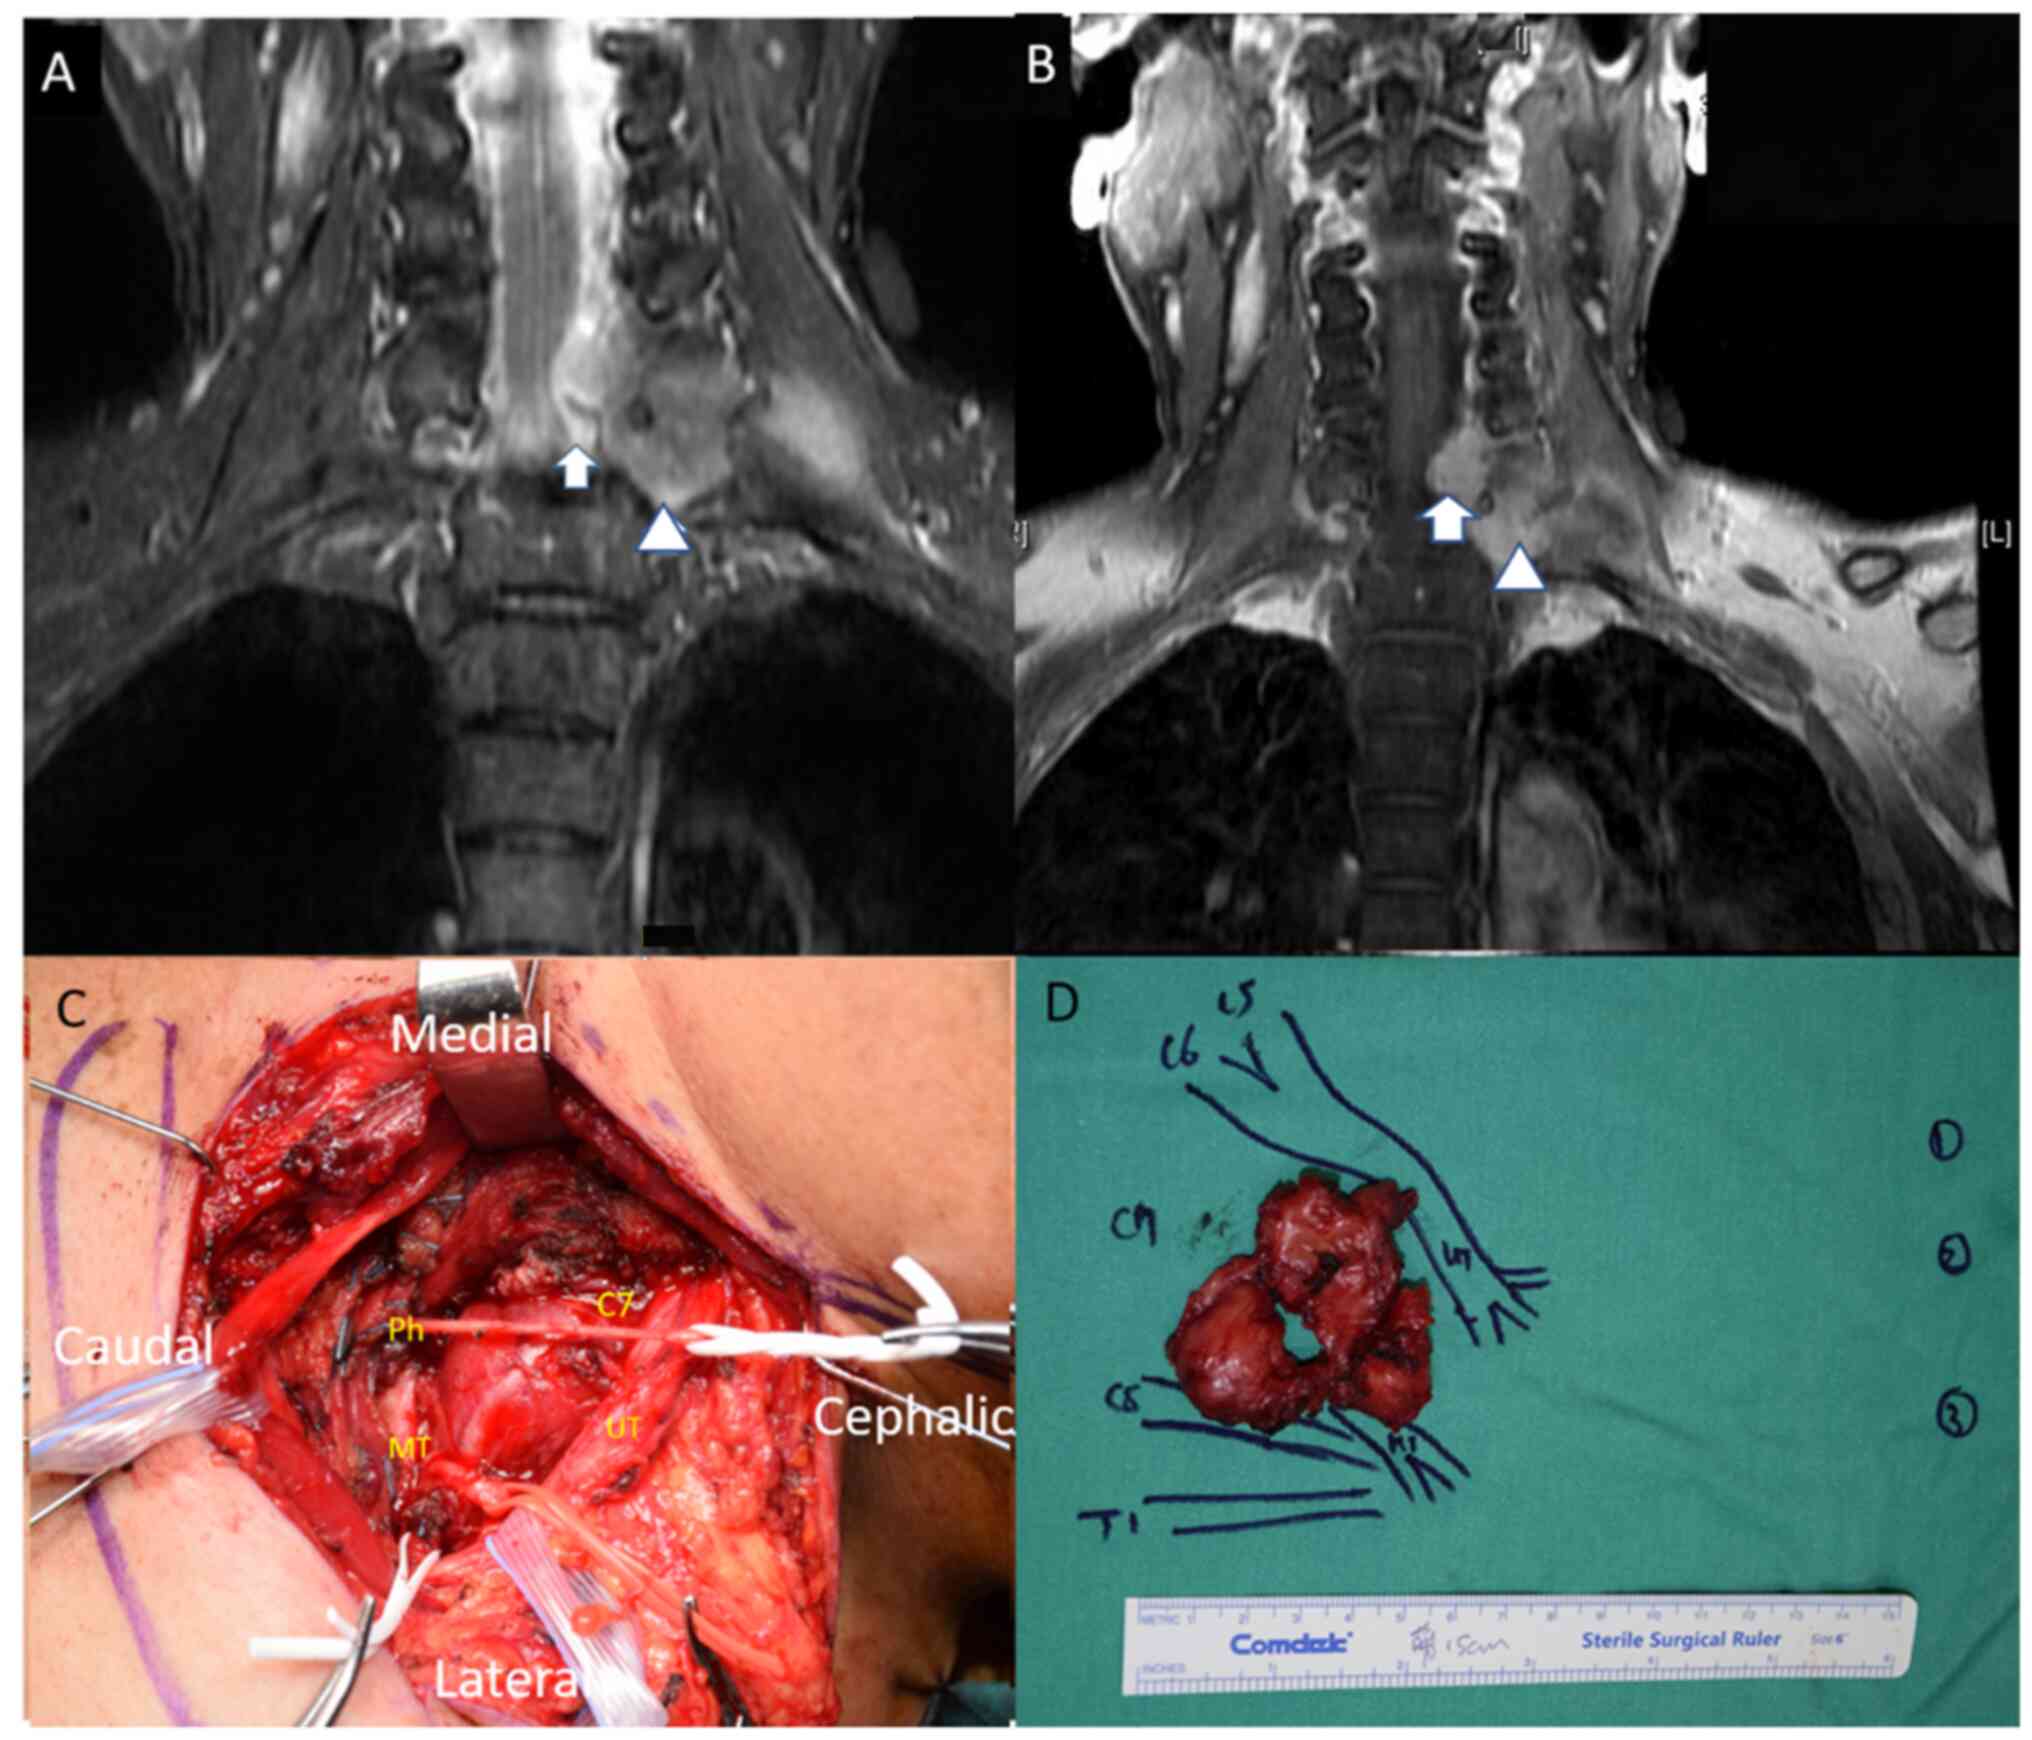

lesion localized to the left 7th cervical root (Fig. 1). Magnetic resonance imaging (MRI)

further revealed a hyperintensity fusiform mass measuring 5.5x6 cm

on T2-weighted short inversion time inversion recovery sequences.

The mass extended from the left 6/7th cervical to the 7th

cervical/1st thoracic neural foramens and reached into the left

brachial plexus. Additionally, T1-weighted images with contrast

demonstrated an enhanced mass extending into the left brachial

plexus accompanied by compression on the spinal cord (Fig. 2A and B).

Based on these findings, the presumptive diagnosis

before surgery was schwannoma or malignant nerve sheath tumor.

An incomplete tumor excision was performed due to

the encasement of the tumor around the vertebral artery. This

intervention involved a laminectomy of the 6 and 7th cervical

vertebrae, an excision of the 7th cervical nerve root, a phrenic

nerve transfer and neurolysis of the 8th cervical spinal nerve.

Intraoperative observations and gross pathology revealed tumor-like

masses (Fig. 2C and D).